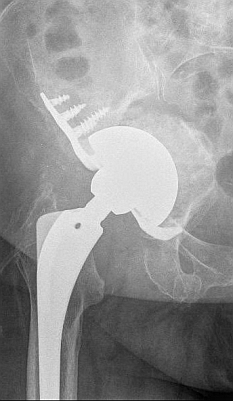

Die Komponenten einer klassischen Geradschaftprothese: Prothesenschaft, Prothesenkopf, Pfanneninlay aus Polyethylen und Hüftpfanne. © Implantcast